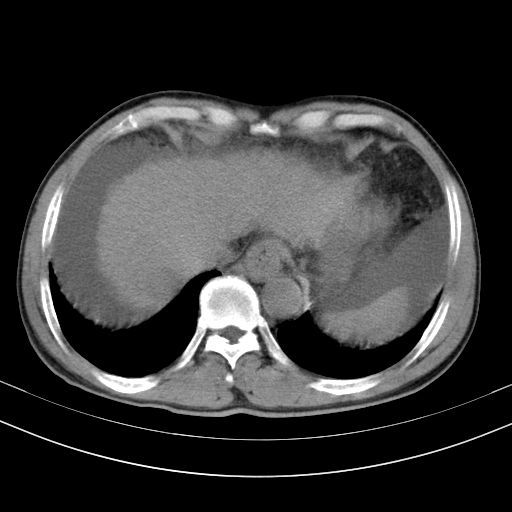

以下是引用随光逐影在2010-2-28 10:23:00的发言:[br]1)考虑肝癌;建议行ct增强扫描检查。2)肝硬化,脾大,腹水。3)慢性胆囊炎。